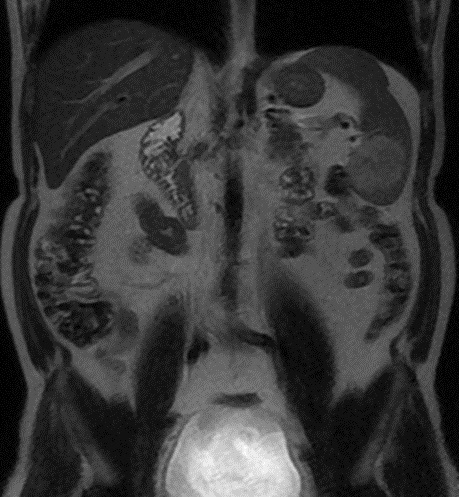

Image radiologique TDM en coupe coronal

d'une splenomegalie . La rate est tres volumineuse

compress angle colique gauche et le rein gauche à

inferieuse , La coupole diapragmatique est

legerement pousse en haute . On peut en s'observe

image de plaque de infartus parenchymateuse

hypodense à bord inferieuse de la rate |